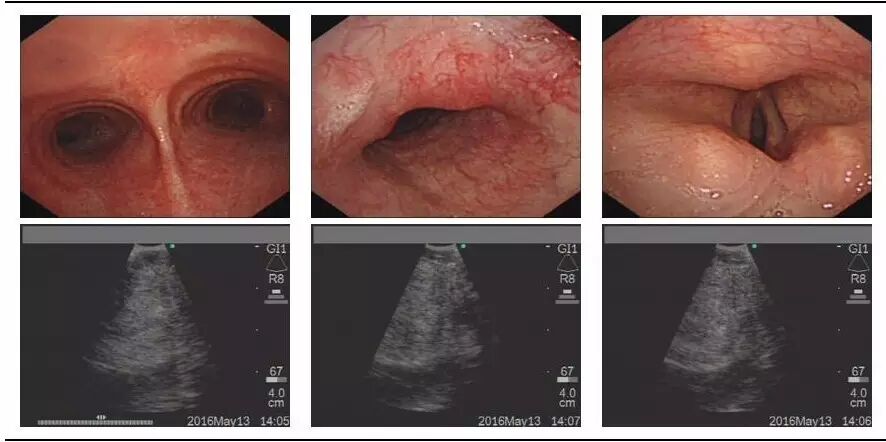

54岁男性,既往做过左侧甲状腺手术,此次因颈前肿物就诊,B超和CT均提示甲状腺癌可能,II、III、IV、VI区淋巴结可疑转移。超声支气管镜下可见肿物位于声门下约1.5cm气管左前壁,并且和气管分界不清(图1);而在食管镜下发现,肿物位于甲状腺左侧,与气管、食管壁分界不清,侵犯至食管粘膜下层,肿物最大切面3.63cm×3.80cm。

图1  超声支气管镜